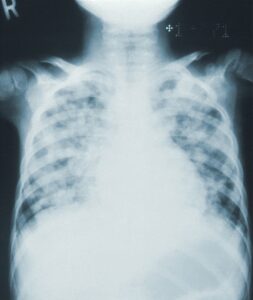

The following video was published in march 2020 by Keith Mortman, chief of the division of thoracic surgery in the George Washington university hospital.

It uses 360 degree virtual reality technology to show the damage done to the lungs of a COVID-19 patient. And even if we call it “virtual” reality, the video is based on real data from a real patient.

This video allows health professionals to understand how the virus spreads. Therefore, they can fight it more efficiently. But Keith Mortman thinks that the general public can watch it too, to understand the damage made by COVID. In the video, the yellow parts are the ones infected by COVID. “It shows a stark contrast between the virus infected abnormal lung tissue and the more healthy adjacent lung tissue.”

We all know that, in the most severe cases, COVID can cause respiratory distress leading to death. But with this 3D representation, doctor Mortman wanted to  actually show the damages caused by the virus on the lungs.